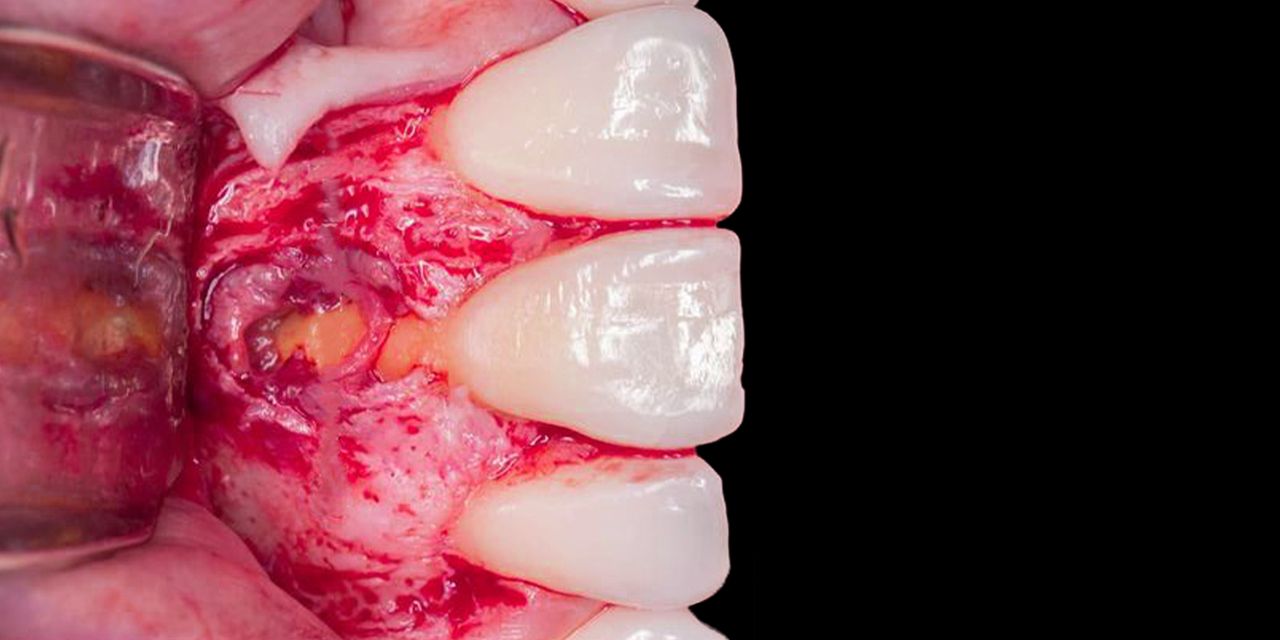

Retro-preparation and sealing: step-by-step protocols

– Clinical aspects of strategic treatment planning;

– Pain control in apical surgery:

- Premedication

- Local anesthesia

- Postoperative therapy.

– Flap design: paramarginal vs full muco-periosteal flap;

– Features of creating access to a pathological focus near:

- Chin hole,

- Maxillary sinus,

- Inferior alveolar nerve.

– Deep apical dissection technique;

– Strongly curvature of the roots: features of resection of the root tip;

– Isthmuses: classification and features of retrograde filling;

– Tools for retrograde root canal preparation: NiTi condenser;

– Apical cracks: tactics and prevention;

– Silers and compaction techniques of materials;

– Intentional reimplantation.